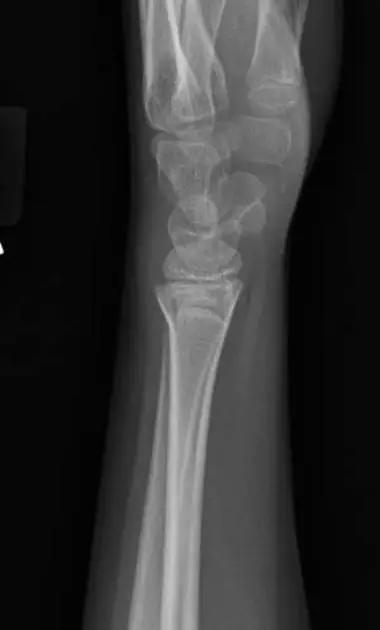

3. Smith 骨折

桡骨远端骨折伴骨折远端向掌侧移位,也称为反 Colles 骨折。

来源:radiology assistant